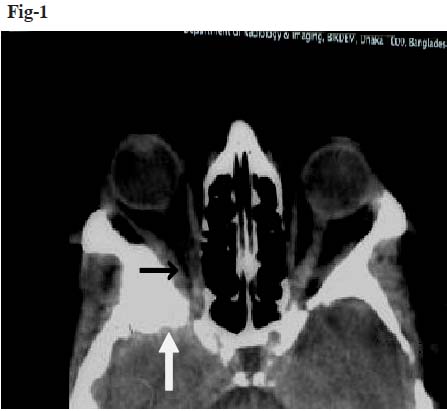

A 42 year old female presented with history of gradual protrusion of the right eye for two years with complete loss of vision of the same eye for the last two months. The patient was referred to Department of Radiology and Imaging, BIRDEM from the Department of Neurosurgery, BSMMU. She had history of itching of both upper and lower eyelids for one and half years and gradual dimness of vision of the right eye for last six months. Fundus examination of right eye revealed that there was temporal disc pallor with bulging of the optic disc. There was no motor or sensory in-coordination, gait deficit or any asymmetry in reflexes. She was mildly anemic. The biochemical investigations were unremarkable. Computerized tomography (CT) of the brain and orbit with and without contrast revealed iso-dense soft tissue mass in right infra temporal fossa along the lateral wall of the right orbital cavity displacing the right optic nerve to the left (Figure 1). The mass revealed strong homogenous enhancement. Bone window of CT showed hyperostosis and gross thickening with hazy margin of greater and lesser wings of the sphenoid bone, frontal process of zygomatic bone and adjacent part of squamus part of temporal bone on the right side. There was irregularity of inner table of the affected bones. CT findings suggested right sphenoidal meningioma with intraorbital, extracranial and infratemporal components. Thickening of right lateral and superior recti muscles were demonstrated. Polyostotic fibrous dysplasia was also suspected as differential diagnosis. MRI of the brain with orbit (T1 axial, sagittal and T2 axial) was done with and without gadolinium-DTPA scan. Irregular frank expansion and deformity of right sphenoidal wing, petro-temporo-zygomatic bone with intermediate signal intensity in T1WI and T2WI was demonstrated. There was strong contrast enhancement of the lesion (Figure 2). There was also linear thick nodular enhancement involving the dura overlying the right temporoparietal lobes. Right orbital canal and orbital fissure were narrowed with encroachment of right optic nerve. The finding was indicative of intraosseus meningioma.

Fig-2. MR image in T1 (contrast) weighted sequence showing irregular frank expansion and deformity of right sphenoidal wing suggesting possibilities of intraosseus meningioma, bony neoplasm or polyosteotic fibrous dysplasia.